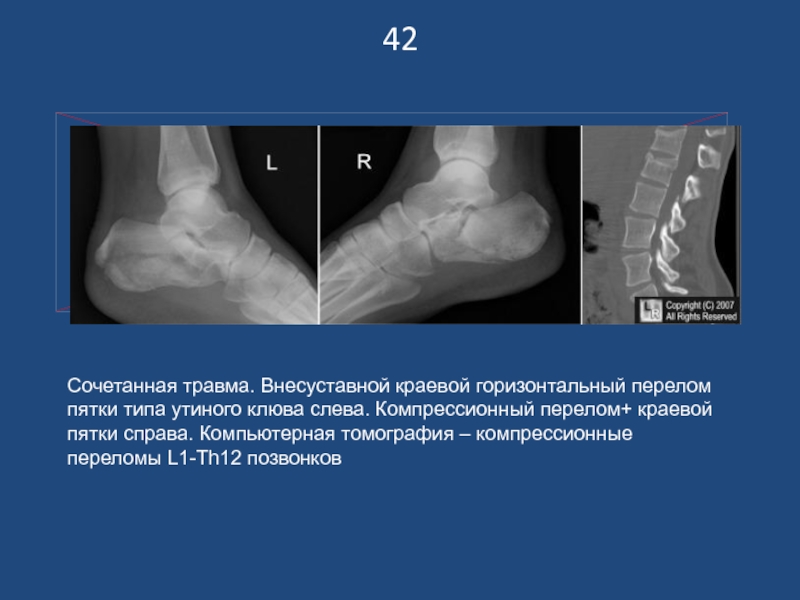

Слайд 4342

Сочетанная травма. Внесуставной краевой горизонтальный перелом пятки типа утиного клюва

слева. Компрессионный перелом+ краевой пятки справа. Компьютерная томография – компрессионные

переломы L1-Th12 позвонков